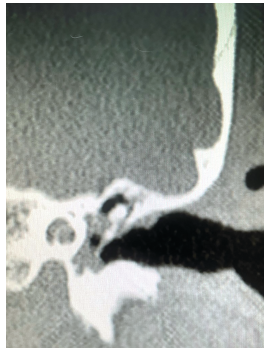

Introduction: Heterotopic Brain and Encephaloceles of middle ear usually present with symptoms of ear discharge and hearing loss. Some patients have additional symptoms of headache, abnormal ringing sensation and vertigo. Radiology may or may not show a communication with central nervous system in encephaloceles and the bony defect may be unnoticeable or attributed to the thinning of bone due to chronic otitis media. On computerised tomography, no distinction may be made between fluid, granulations, cholesteatoma and other space occupying lesions. Morphologically, it may be identified grossly if it presents with its characteristic pink colour and typical convoluted cerebriform pattern (CCP).  Methods: A 26 years female presented to us with unilateral ear discharge since birth and unilateral hearing loss on ipsilateral side for last 18 months. Clinically, radiologically and morphologically it mimicked chronic otitis media with cholesteatoma with no pre-operative and intra-operative distinction from the later. However, the coronal section at the level of anterior tegmen showed a small defect of the tegmen. T2 weighted MRI confirmed presence of brain tissue in middle ear and mastoid cavity. Results: Combined Middle Cranial Fossa and mastoid approach were employed, unviable brain tissue was excised and sent for histopathology. Viable brain tissue was reduced and tegmen defect was closed with temporalis muscle, conchal cartilage and temporalis fascia. Histopathology revealed glial tissue, ependyma and choroid plexus without any cholesteatoma. Conclusion: Tympanic encephalocelesare very rare and may closely mimic chronic otitis media. It may become very difficult to differentiate between the two which may lead to unexpected complications andloss